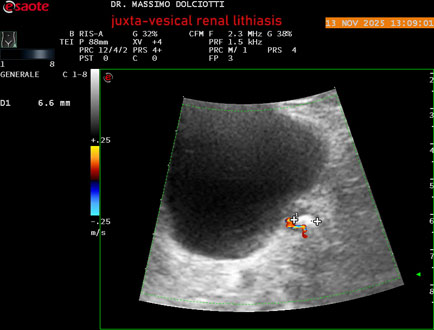

Data inserimento: 14/11/2025

Ecografia del: 13/11/2025

Strumento: Esaote MyLab Eight

Sonda: Convex Multifrequenza 1-8 MHz

Età Paziente: M 59 anni

Motivazione dell'esame: dolori al basso addome ed al fianco sinistro, comparsi la notte precedente.

Commento all'esame: le immagini ed il video documentano al rene sinistro, idronefrosi di 1°-2° grado, con presenza di immagine iperecogena, con cono d'ombra posteriore, allo sbocco dell'uretere sinistro, in sede iuxta-vescicale, delle dimensioni di 6,2 mm, con segno del Twinkling Artifact (o segno di Arlecchino), da ricondurre a litiasi.

Conclusioni: litiasi renale sinistra iuxta-vescicale (left juxta-vesical renal lithiasis).